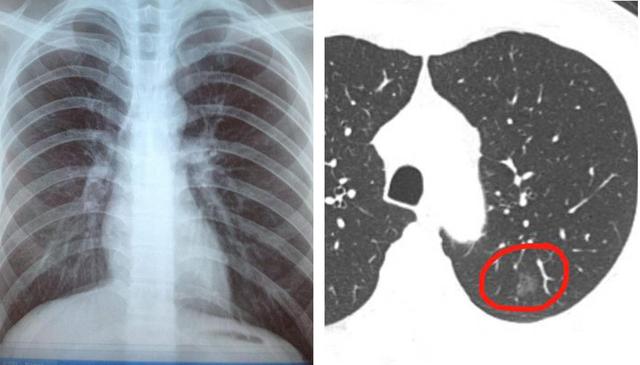

再次回归现实中的一例早期肺癌患者,这名患者前面单位体检拍胸片未见异常,随后因其他原因行胸部CT检查,无意中发现一枚磨玻璃结节,最后手术结果显示为早期肺癌。如下图:左侧胸片中完全看不到的肺部结节,而右图胸部CT的其中一个层面能看到胸膜下9mm的肺部磨玻璃结节灶。